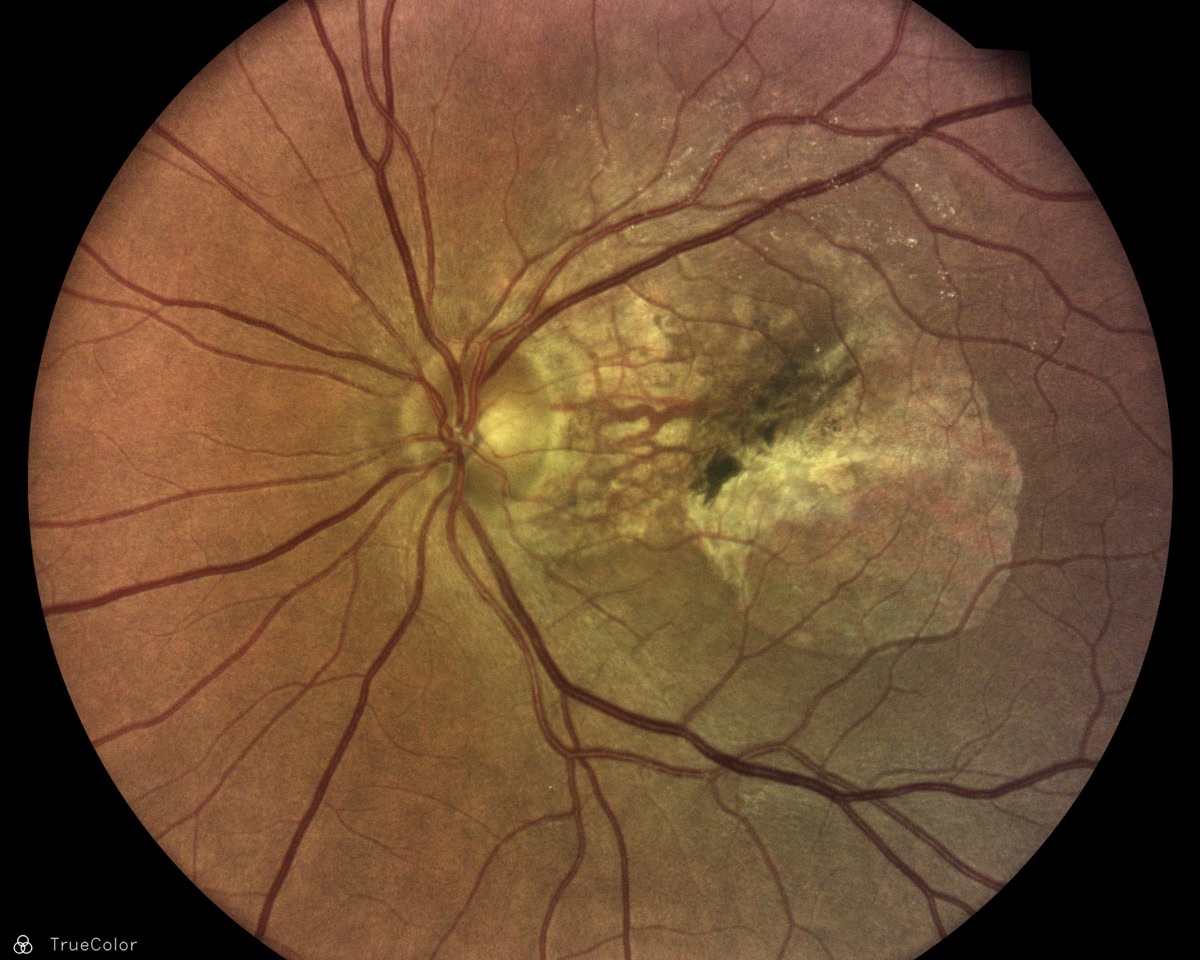

TrueColor Confocal Imaging Examples

High-resolution retinal images captured with the iCare DRSplus — 10 megapixels at 77 pixels/degree, fully automated and non-mydriatic.

TrueColor fundus image showing age-related macular degeneration

Age-Related Macular Degeneration — TrueColor confocal

Clinical images courtesy of iCare / Revenio Group. All images captured non-mydriatic.